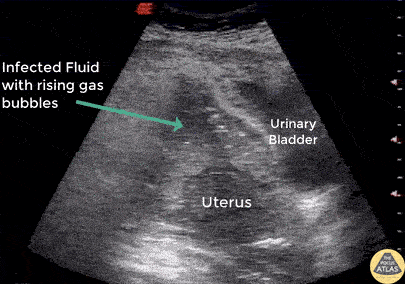

A patient presented to the ED 4 days s/p pregnancy termination via D&C with a fever and profound hypotension. POCUS revealed pelvic free fluid with rising gas bubbles indicative of a uterine perforation. Image courtesy of Robert Jones DO, FACEP @RJonesSonoEM Director, Emergency Ultrasound; MetroHealth Medical Center; Professor, Case Western Reserve Medical School, Cleveland, OH View his original post here